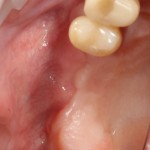

В прошлый раз мы с вами говорили о сочетании имплантации и остеопластики методом аутотрансплантации крупных костных фрагментов. Сегодня мы продолжим тему и поговорим о сочетании имплантации и остеопластики методом направленной костной регенераци (НКР), что встречается гораздо более часто и, на первый взгляд, выглядит более естественно. Вот ситуация до операции: